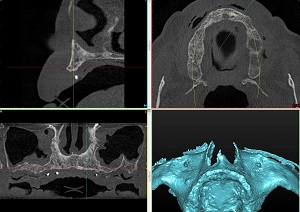

Implant planning begins with a jaw scan, cone beam computed tomography (CBCT) and a blood test. The dentist compares the results and determines the optimal position of the implants, the type of bone, the position of the dental system, the need for augmentation (bone buildup) or sinus lifting.